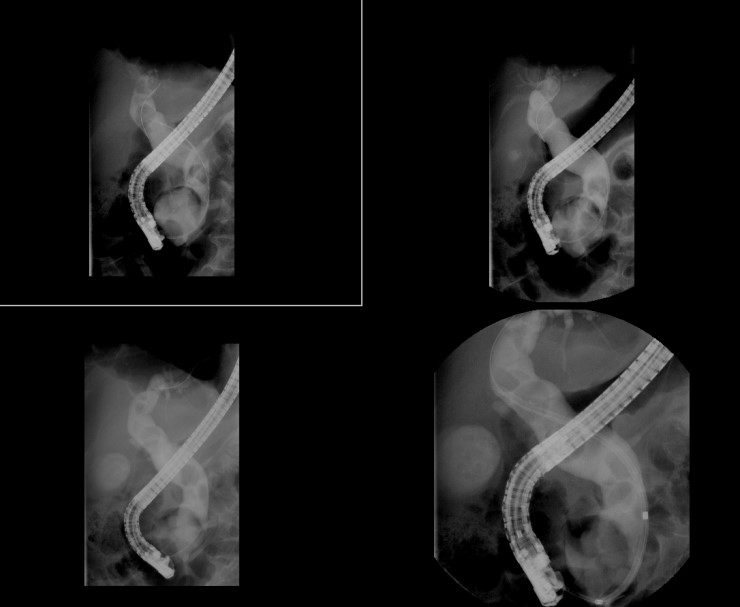

Figure 031_0351. Endoscopic retrograde cholangiopancreatography (ERCP) with stone extraction Endoscopic Retrograde Gallbladder Drainage Endoscopic management of acute cholecystitis has expanded in patients who are considered nonoperative candidates. Endoscopic gallbladder drainage can be considered in patients without evidence of gallbladder perforation or biliary peritonitis. Endoscopic retrograde cholangiopancreatography (ercp) is an invasive procedure used for the diagnosis and treatment of obstruction in the biliary system. Two endoscopic approaches to gallbladder drainage exist, they include a. Endoscopic Retrograde Gallbladder Drainage.

Endoscopic retrograde cholangiopancreatography (ERCP) catheter was... Download Scientific Diagram Endoscopic Retrograde Gallbladder Drainage Endoscopic management of acute cholecystitis has expanded in patients who are considered nonoperative candidates. Endoscopic gallbladder drainage can be considered in patients without evidence of gallbladder perforation or biliary peritonitis. Two endoscopic approaches to gallbladder drainage exist, they include a transmural approach performed with. Endoscopic retrograde cholangiopancreatography (ercp) is an invasive procedure used for the diagnosis and treatment of obstruction. Endoscopic Retrograde Gallbladder Drainage.